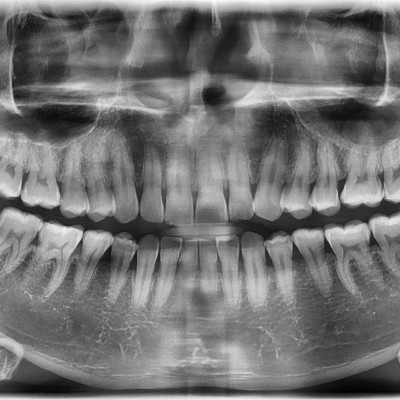

매복사랑니 발치 구강외과전문의가 직접 발치합니다.

작성자 이턱이 작성일 01-15 조회 29